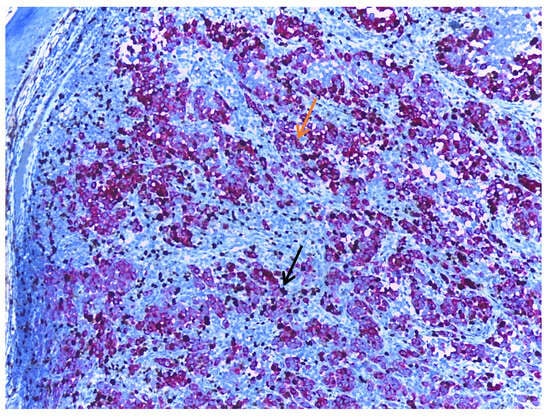

- Ronchi, A.; Cazzato, G.; Ingravallo, G.; D’Abbronzo, G.; Argenziano, G.; Moscarella, E.; Brancaccio, G.; Franco, R. PRAME Is an Effective Tool for the Diagnosis of Nevus-Associated Cutaneous Melanoma. Cancers 2024, 16, 278. [Google Scholar] [CrossRef] [PubMed]